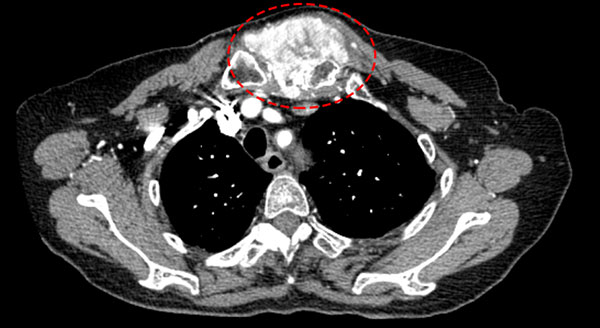

(肿瘤巨大严重侵蚀胸骨)

考虑到患者80多岁高龄,手术具有高危风险,张余主任带领的骨肿瘤团队迅速组织了院内多学科会诊(MDT),邀请耳鼻喉头颈外科主任张思毅、肿瘤内科马海清主任、李伟雄主任、影像科周正根主任,共同制定手术方案。周正根主任阅片后,确认患者肿瘤纵横径达7cm,肿瘤巨大,切除范围广泛,且肿瘤邻近心脏、周围大血管及重要神经组织,手术当中应当谨慎操作。马海清主任、李伟雄主任认为患者肿瘤来源于甲状腺,手术当中需一并切除甲状腺组织。此外肿瘤切除后缺损较大,需联合胸外科及烧伤与创面修复科合作实施手术,另外还提前与麻醉科室、ICU科室深入沟通。